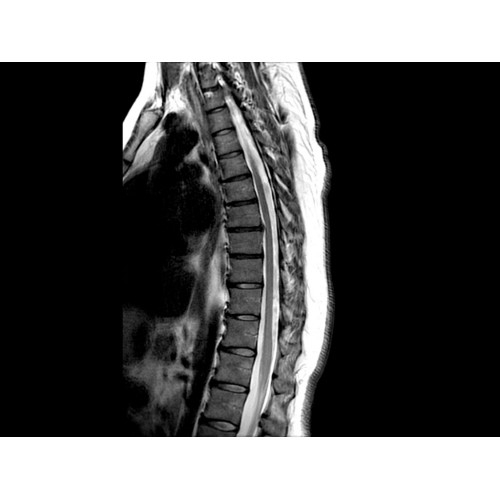

• Визуализация всего позвоночника слиянием двух участков — получить изображение всего позвоночника можно намного быстрее.

МРТ аппарат GE Optima MR450w 1.5T

МР-томограф с широким туннелем Optima MR450w является настоящей рабочей лошадкой и может эффективно обслуживать большее число пациентов. Томограф обеспечивает одновременно удобство пациента, продуктивность работы, отличное качество изображения. В этой МРТ-системе инженерам компании удалось без компромиссов совместить необходимый объем перемещения с удивительно высоким качеством изображения.

Благодаря принципиально новым технологиям мы расширили возможности МР-томографов с широкими туннелями, совместив непревзойденное качество изображений с высокой производительностью при широком — 50 см — поле зрения.

МР-томограф Optima MR450w позволяет получать изображения исключительно высокого качества, которые помогают установить диагноз. Чтобы удовлетворить ожидания клиентов в отношении высокого качества, в МР-томографе Optima MR450w были сохранены дополнительные возможности платформы Discoverу, привнесшие в его работу универсальность и мощь.